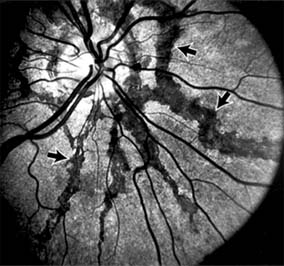

ANGIOID STREAKS

Angioid streaks appear as irregular, jagged tapering lines that radiate from the peripapillary retina into the macula and peripheral fundus (Figure 10-9). The streaks represent linear crack-like dehiscences in Bruch's membrane. The lesions are rarely noted in children and probably develop in the second or third decade of life. Early in the disease the streaks are sharply outlined and red-orange or brown. Subsequent fibrovascular tissue growth may partially or totally obscure the streak margins.

Figure 10-9

Figure 10-9: Multiple angioid streaks (arrows) extend from the optic nerve. (Courtesy of University of California, San Francisco.)

Nearly 50% of patients with angioid streaks have an associated systemic disease. Pseudoxanthoma elasticum, Paget's disease of bone, Ehlers-Danlos syndrome, and several hemoglobinopathies and hemolytic disorders have been associated with this retinal disease, but the most common association is with age-related degeneration of Bruch's membrane. Patients with angioid streaks should be warned of the potential risk of choroidal rupture from even relatively mild eye trauma. Older patients with the disease are at risk of developing serous and hemorrhagic detachments of the retina as a consequence of subretinal neovascularization.

Laser treatment may be used to photocoagulate extrafoveal neovascular membranes; however, other neovascular membranes are likely to occur. Prophylactic treatment of angioid streaks before subretinal neovascularization develops is not recommended.